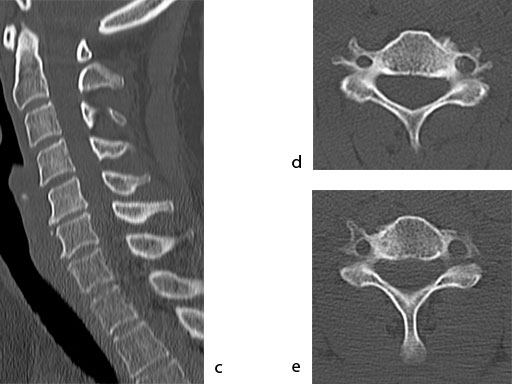

A 51-year-old woman was affected by cervical radiculo-myelopathy due to spinal and neuroforaminal stenosis. The preoperative CT scans are shown at Fig 4 and MRI at Fig 5.